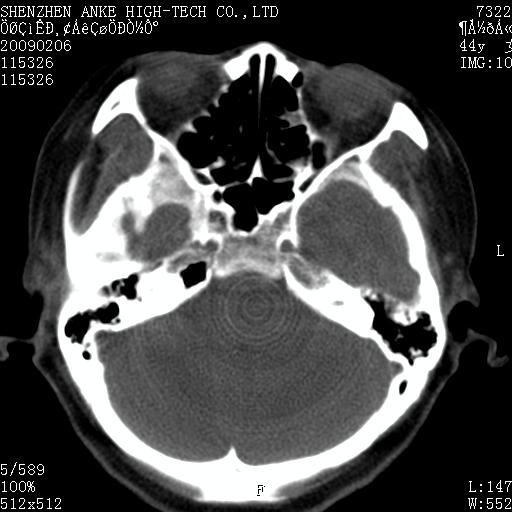

标题: CT17977:女,44岁,右侧颌部包块1年,右侧面瘫2月。 [打印本页]

患者:女,44岁,右侧颌部包块1年,右侧面瘫2月。

考虑右侧腮腺混合瘤可能性大

考虑右侧腮腺混合瘤。

考虑右侧腮腺混合瘤。年轮样伪影考虑机器问题!

右侧腮腺混合瘤可能性大

考虑右侧腮腺混合瘤;不排除腮腺癌。

右侧腮腺肿瘤,良恶性难定。

右侧腮腺混合瘤。机器没有调试好。